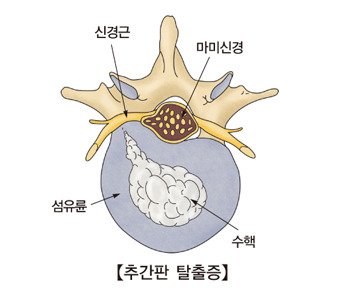

추간판탈출증은 우리가 흔히 알고 있는 디스크라고 불리는 척추 질환 중 하나입니다. 척추뼈와 척추뼈 사이에는 추간판(디스크)가 있으며, 이 디스크가 여러 원인으로 인해 손상을 입게 되면, 추간판 내부에 수핵이 탈출하게 되어 그 주변에 있는 척추신경이 압박되어 통증이 발생하는 신경학적 이상 증세입니다. 갑자기 무거운 물건을 들어 올리는 등 다양한 원인들 중 사고로 인한 급성 허리디스크, 체형의 변형, 노화로 인한 수핵 수분의 감소, 잘못된 자세가 지속되면 발생하는 피로나 스트레스로 인한 만성 허리디스크가 있습니다. 이러한 허리디스크는 요추(lumbar)에서 발생하며, 특히, 체중의 부하가 가장 높은 요추 4번과 5번(L4-5), 혹은 요추 5번과 천추 1번(L5-S1)에서 주로 발생한다고 알려져 있습니다.

추간판은 크게 외부의 섬유 조직인 섬유륜과 내부의 젤리 형태의 수핵으로 구성되고 있습니다. 이 수핵이 디스크라고 불리며, 디스크는 스프링처럼 쿠션 역활을 하면서 충격을 완화시킬 뿐만 아니라, 척추 뼈가 밀리지 않게 하고 뼈들이 서로 부딪히지 않도록 보호하게 됩니다.